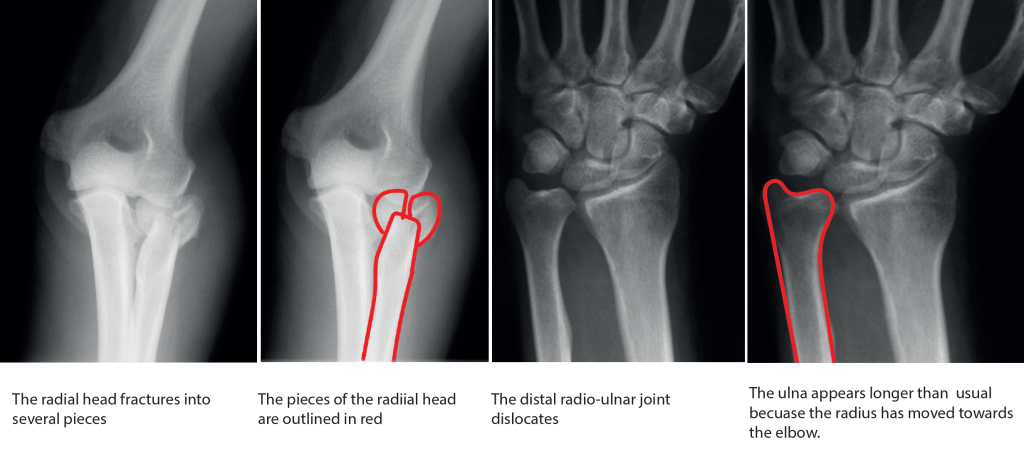

1) The radial head, which often breaks into a number of pieces.

3) The distal radio-ulnar joint, which dislocates when the entire radius bone is driven towards the elbow.

People with this injury usually have pain in their elbow primarily. This often overshadows pain in the forearm or wrist, and may focus attention on the elbow. When a broken or fractured radial head is seen on the first xray, doctors may assume that this is the only injury, and it is for this reason that this injury can be missed initially. A further xray of the wrist will show the characteristic dislocation of the distal radioulnar joint.